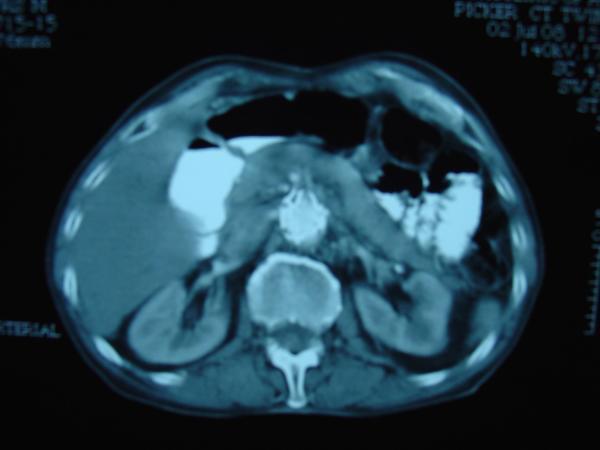

Endovascular repair of anastomotic abdominal aortic aneurysm, after aortobifemoral bypass

Vascular Clinic, Naval and Veterans Hospital of Athens

AVEM2009-Thessaloniki